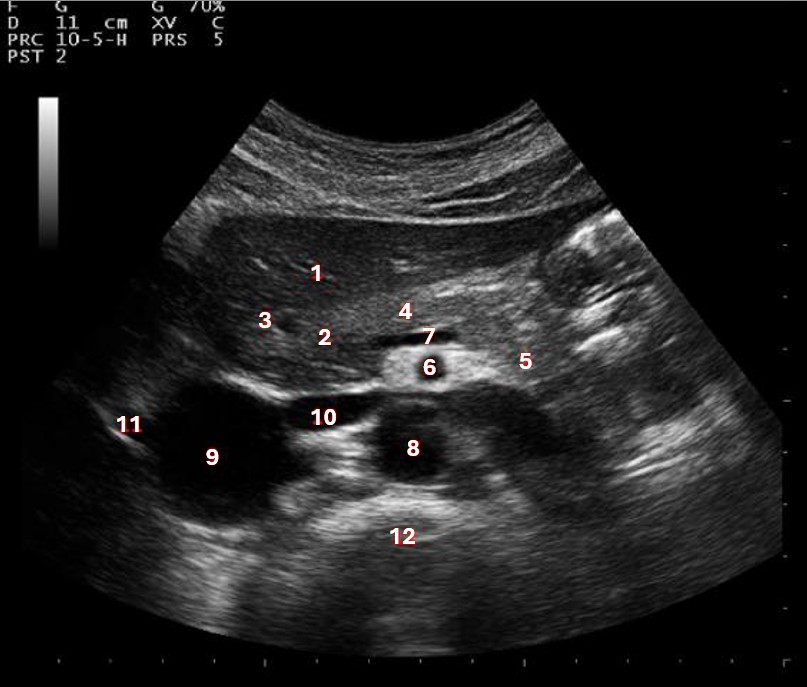

What structure/vessel is indicated by #3?

Gastroduodenal artery

What structure/vessel is indicated by #2?

Head of pancreas

What structure/vessel is indicated by #1?

Medial branch of LPV

What structure/vessel is indicated by #6?

Superior mesenteric artery

Left portal vein

What structures last vessel is indicated by #4?

Medial left lobe

Which of the following structures is labeled #8?

Posterior right lobe

What structures/vessel is indicated by #5?

Tail of the pancreas

What structure/vessel is indicated by #12?

Spine

Which structure/vessel is indicated by #4?

Body of the pancreas

Lateral branch of LPV

What structure/vessel is indicated by #7?

Splenic vein